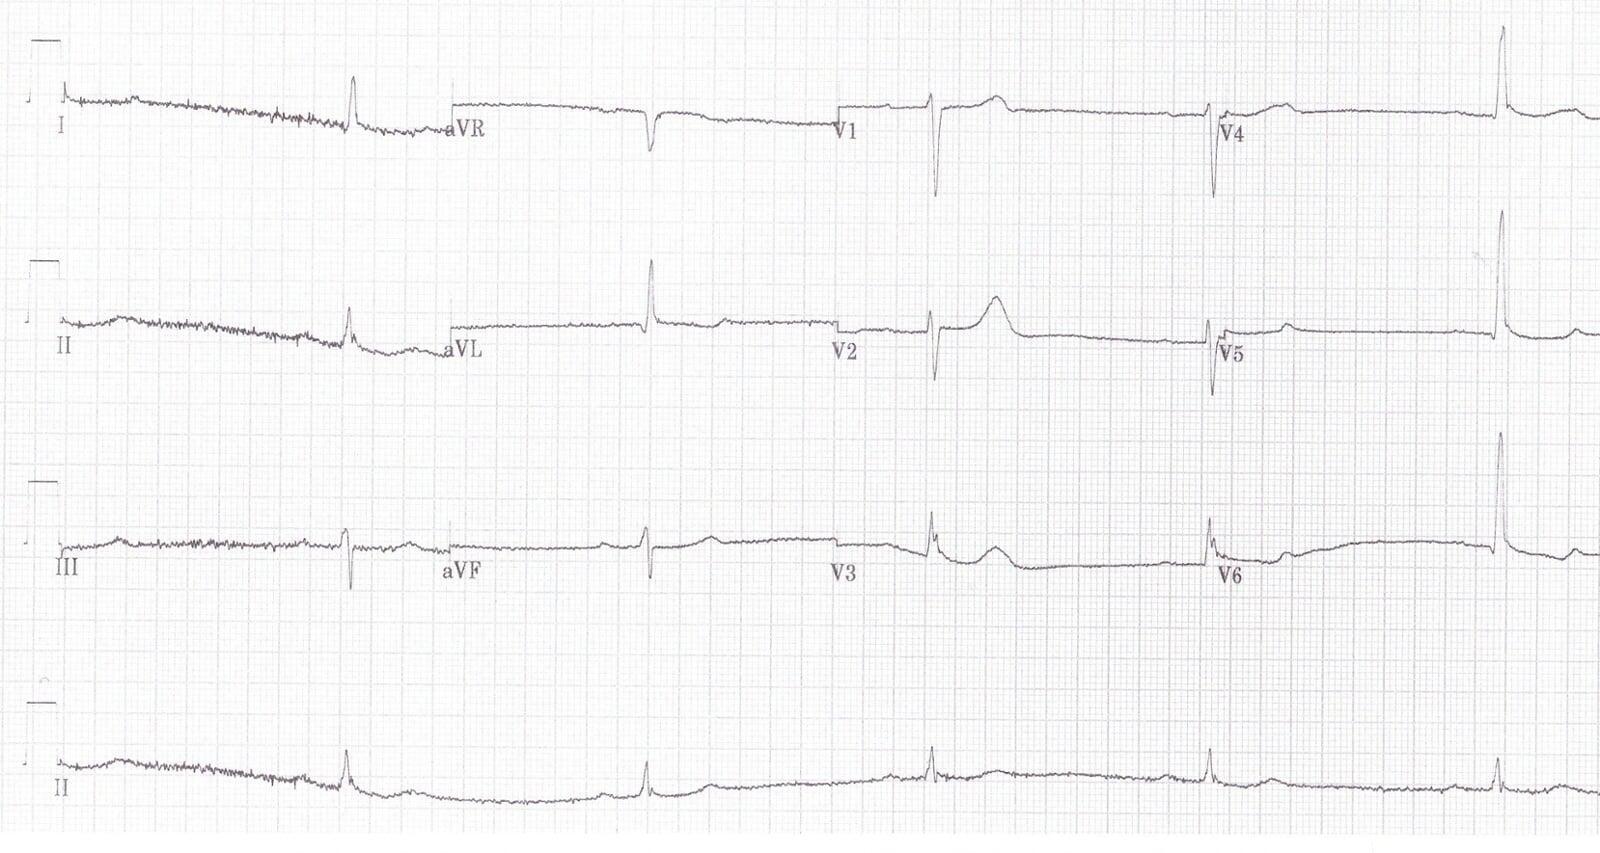

Can you guess what the reason was for the abnormalities in this ECG?

1. Prolonged QTc (QTc = 523 ms)

Osborn Waves (J-Waves)

A distinctive wave at the end of the ECG complex stood out:

- Positive in positive complexes

- Negative in negative complexes

Known as Osborn Waves, these occur as deflections at the J-point, most visible in leads V2–V6, and are classically linked to:

Shivering Artifacts

Movement artifacts were noted in leads I and III, consistent with shivering.

Diagnosis: Hypothermia

Combining:

QTc prolongation

Osborn waves